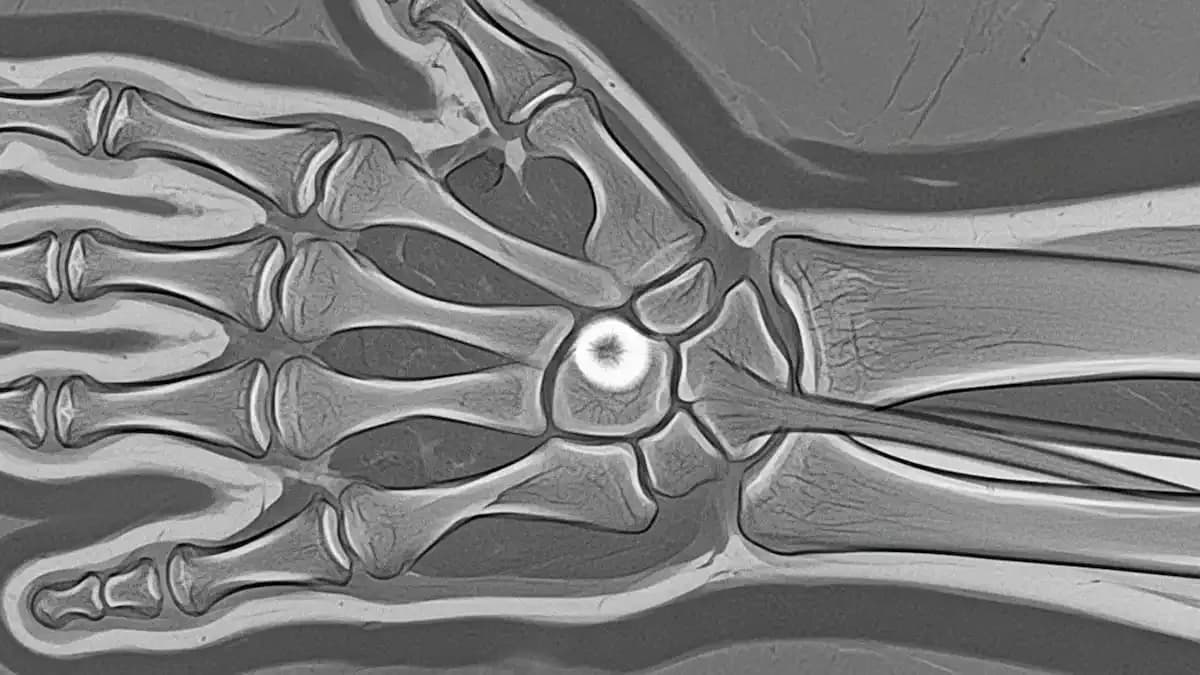

Os exames de imagem complementam: radiografia, ultrassom ou ressonância, conforme a suspeita.

Em casos selecionados, a biópsia é solicitada para confirmar o tipo de lesão antes do tratamento. Essa decisão depende do aspecto da lesão e dos achados nos exames.